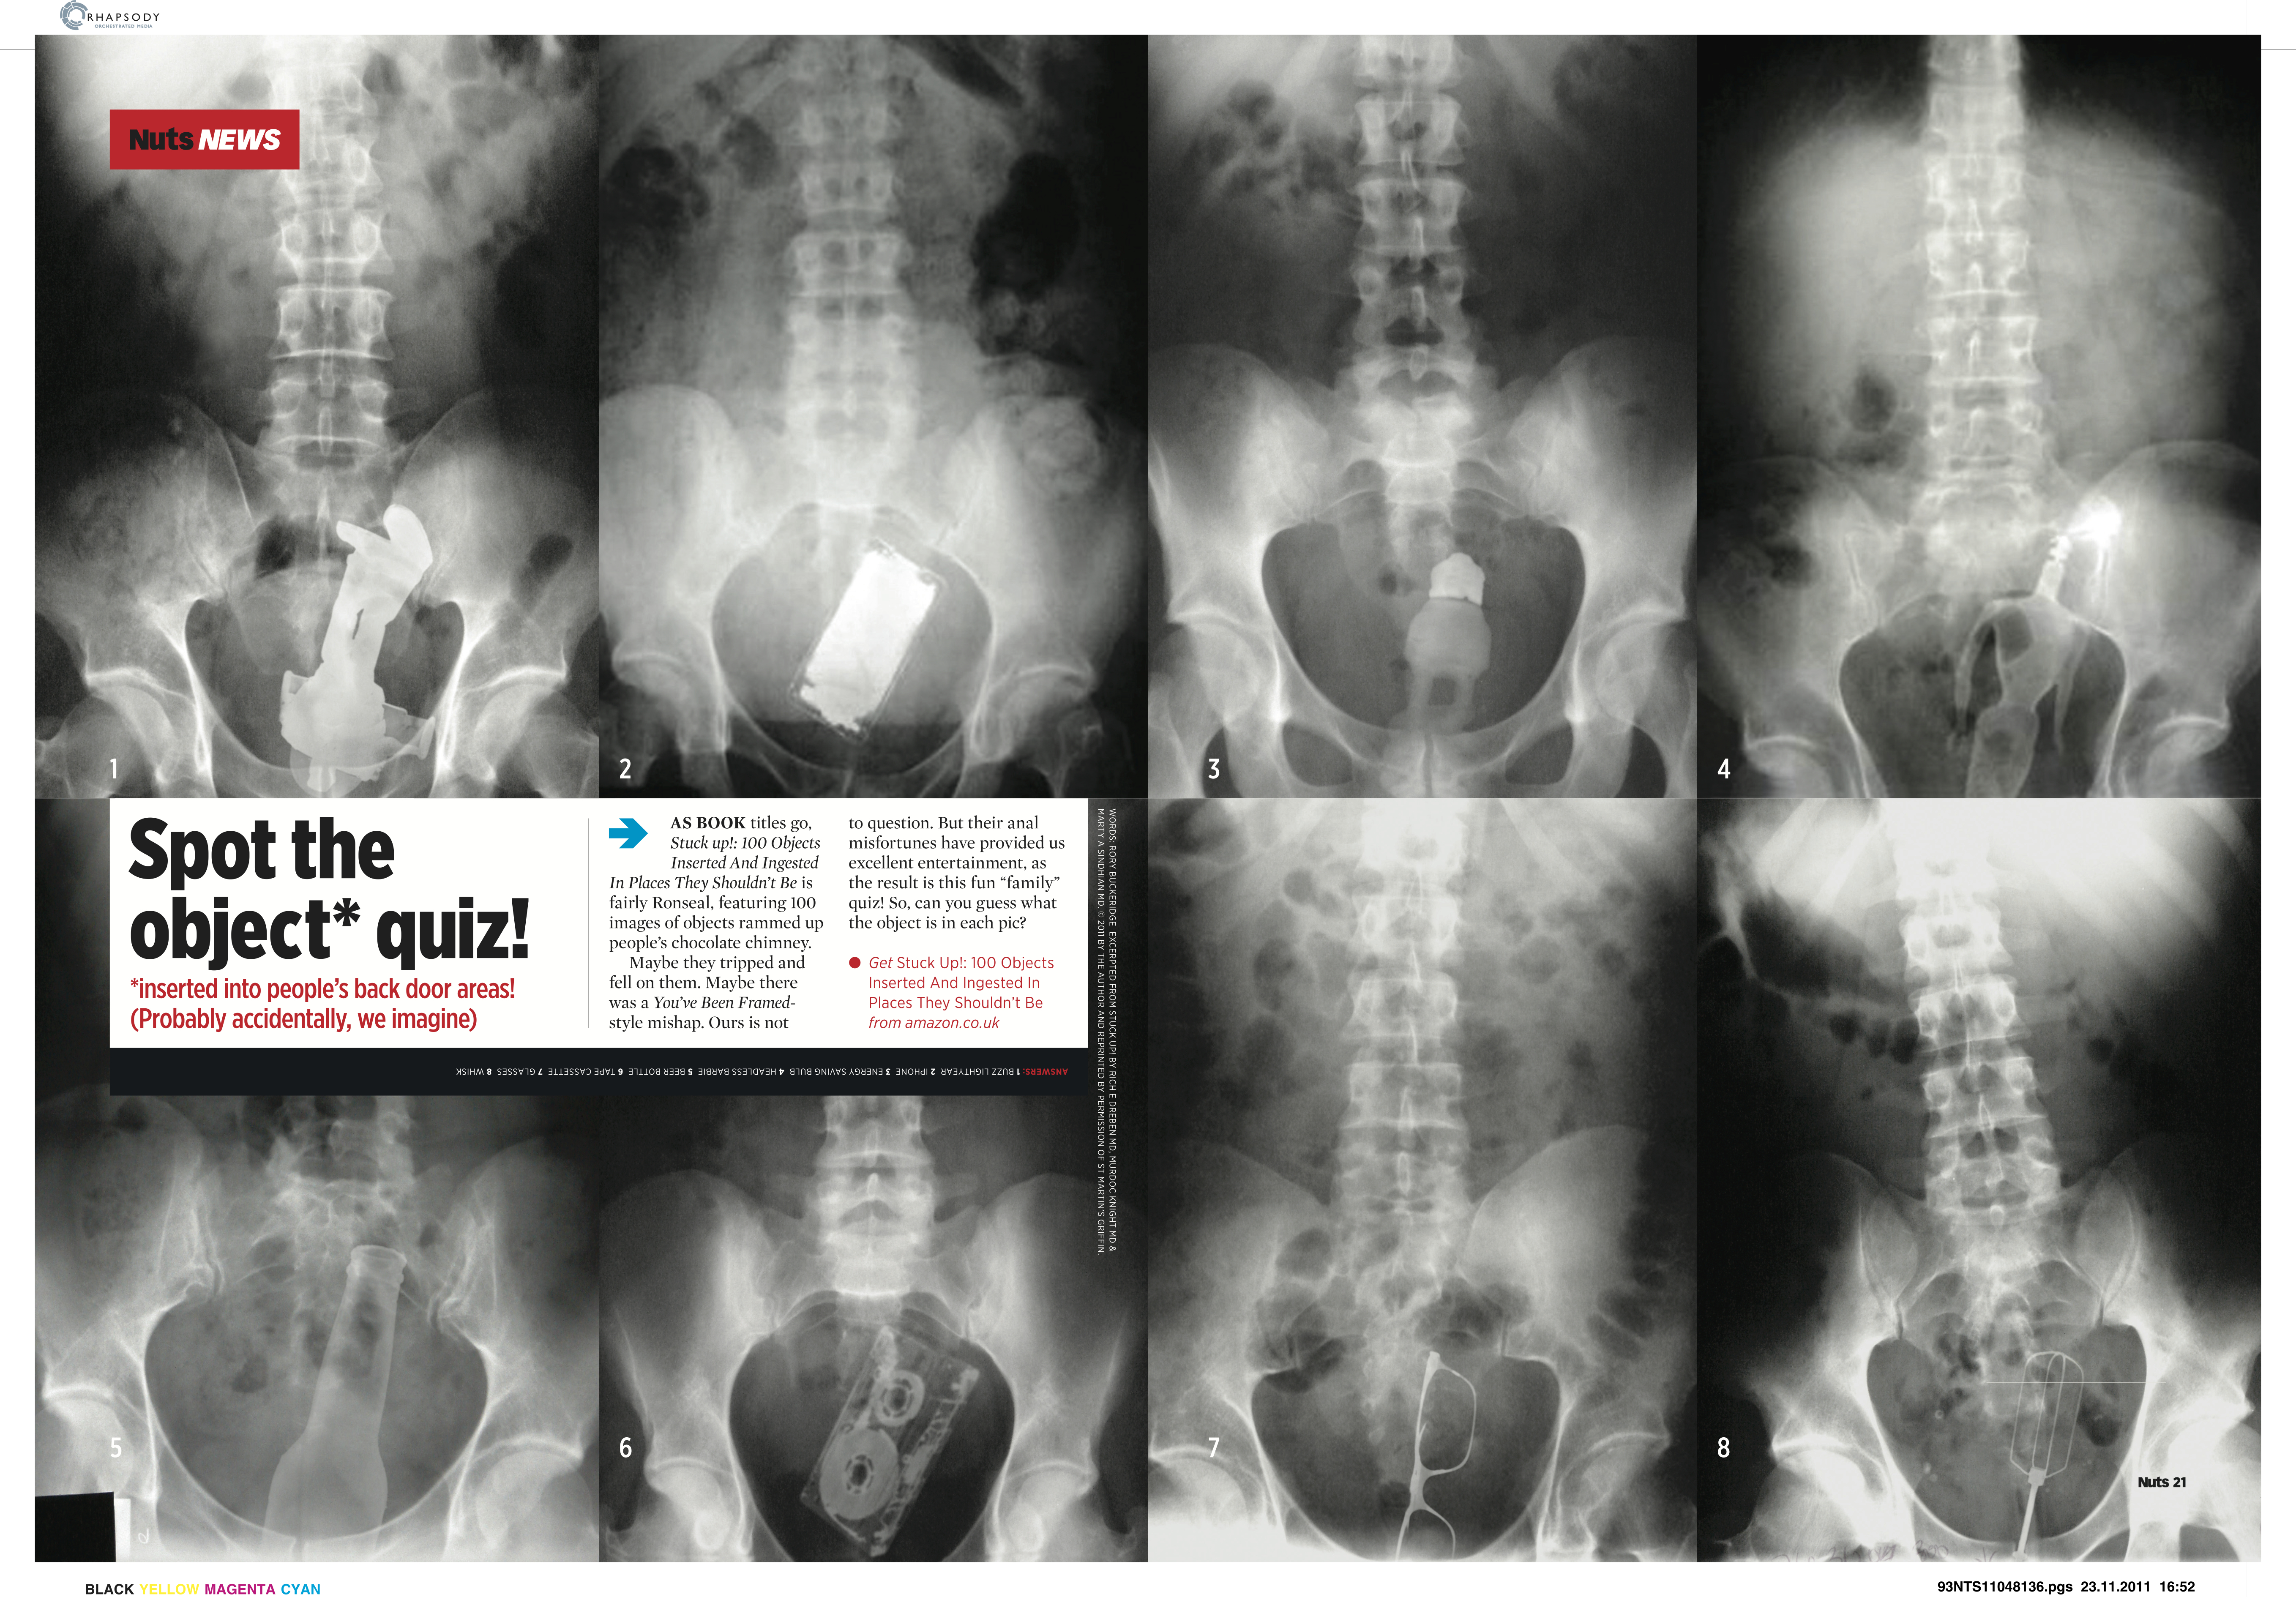

Silly news Date: May 7, 2014Author: rorybuckeridge Post navigation ← Stunts! News stuff → Share this: Share on X (Opens in new window) X Share on Facebook (Opens in new window) Facebook Like Loading... Related